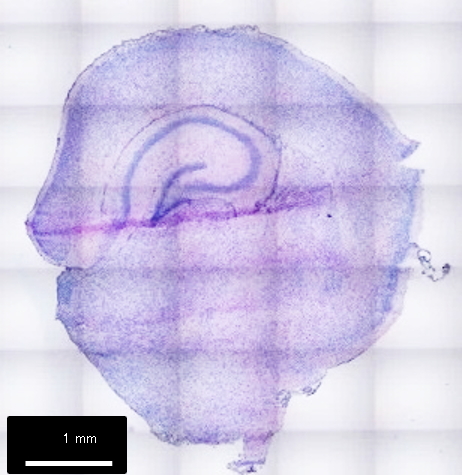

マウス7日齢の脳凍結切片を対象に実施した空間解析の事例をご紹介します。

- マウスP7 右脳 冠状面

- 切片厚 10 μm、組織サイズ約3.5 x 4.9 mm

- シークエンス 1.5G PEリード (DNBSEQ-G400, 1 flow cell)

- 検出遺伝子数 (中央値) 448 (Bin20‐10 μm2 おおよそ1細胞相当)

9,666 (Bin200‐100 μm2)